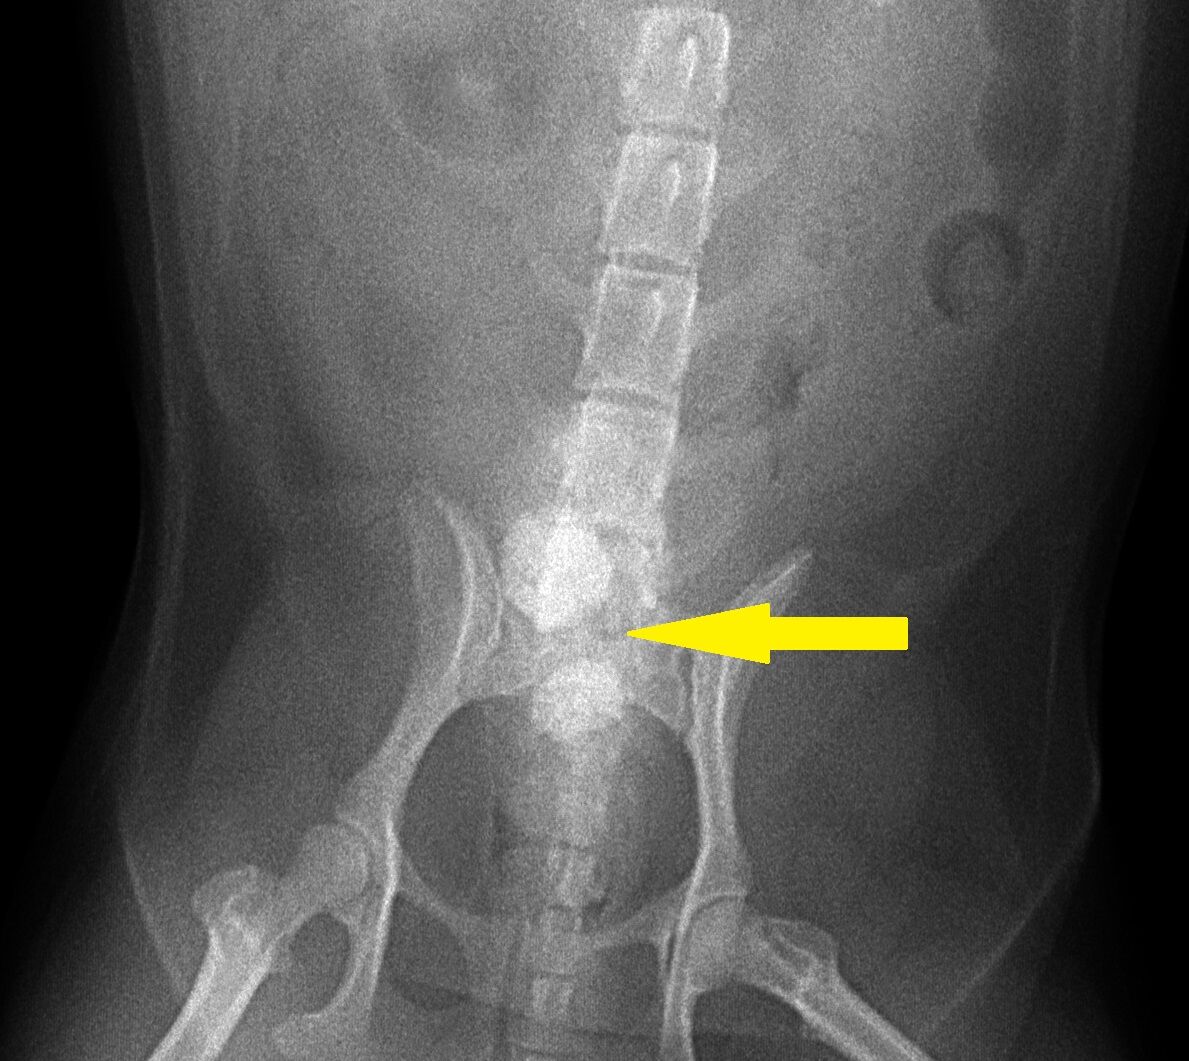

今回はワンちゃんの膀胱結石を取り除く手術について報告させて頂きます。8歳の男の子です。1年ほど前に血尿が出るということで来院されました。その時は尿中に結晶があり、それが原因で血尿が出ていました。その時点では膀胱結石は認められなかったので、内服と膀胱結石の予防用フードで完治しました。尿中の結晶は体質的に出ている可能性があったので、予防用フードを続けることを指示しておりました。しかしその後飼い主さんは来院されることはなく、次に来た時には尿が出にくくなった、とのことで約1年後に来院されました。レントゲンを撮ったところ、下のように膀胱結石が2個できていました。

矢印の丸い2つのものが膀胱結石です。これくらい大きくなってしまいますと手術で取り除いてしまうしかありません。手術して取り除いた結石が下の写真です。